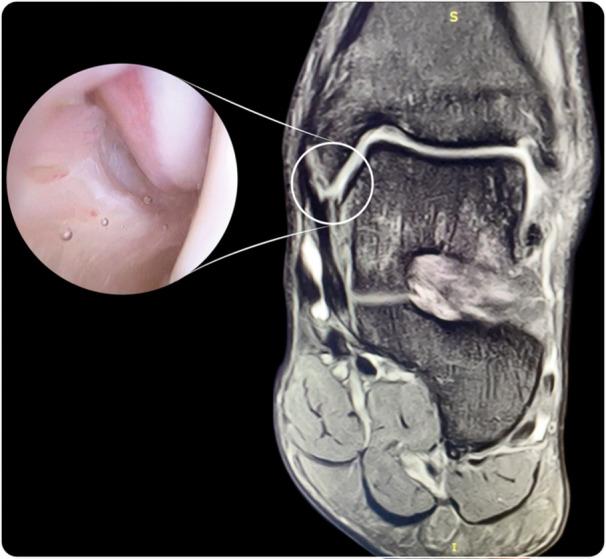

When the intermediate or collicular fascicle of the medial collateral ligament (MCL) is injured, the diagnosis of posttraumatic medial ankle instability (MAI) is supported. The aim of this study was to describe an arthroscopic all-inside MCL repair after posttraumatic MAI secondary to an isolated injury of the MCL deep fascicle with a knotless suture anchor technique.

Seven patients (seven men, median age: 23 [19-28] years) with posttraumatic MAI were treated by arthroscopic means after failing nonoperative management. The median follow-up was 34 (13-75) months. The MCL was repaired with an arthroscopic all-inside technique.

A tear affecting the deep and intermediate or collicular fascicle of the MCL was observed in all cases. In addition, five patients were diagnosed with an isolated fibular anterior talofibular ligament (ATFL) detachment, and in two patients, both the ATFL and calcaneofibular ligament were involved. All patients reported subjective improvement after the arthroscopic ligament repair. The median American Orthopedic Foot and Ankle Society score increased from 68 (range: 64-70) preoperatively to 100 (range: 90-100) at final follow-up.

Posttraumatic MAI can be successfully treated by an arthroscopic all-inside repair of the MCL. The presence of an MCL tear affecting the tibiotalar ligament fibres attached to the area of the anterior colliculus should be considered a sign of posttraumatic MAI. This partial deltoid injury at the level of the intermediate or collicular fascicle will conduct to a dynamic MAI.